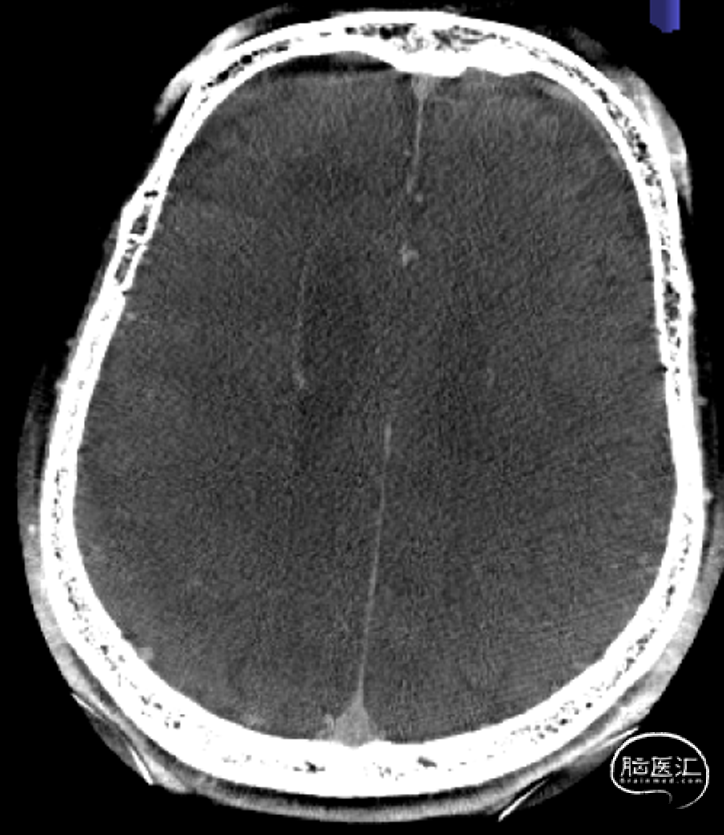

急诊CT(2-22 3:00AM)。